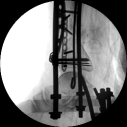

3.在脛骨近端穿入一根克氏針,連接CO外固定架進行固定,并外踝處穿入一根克氏針進行固定。C臂透視位置滿意,縫合結束手術。